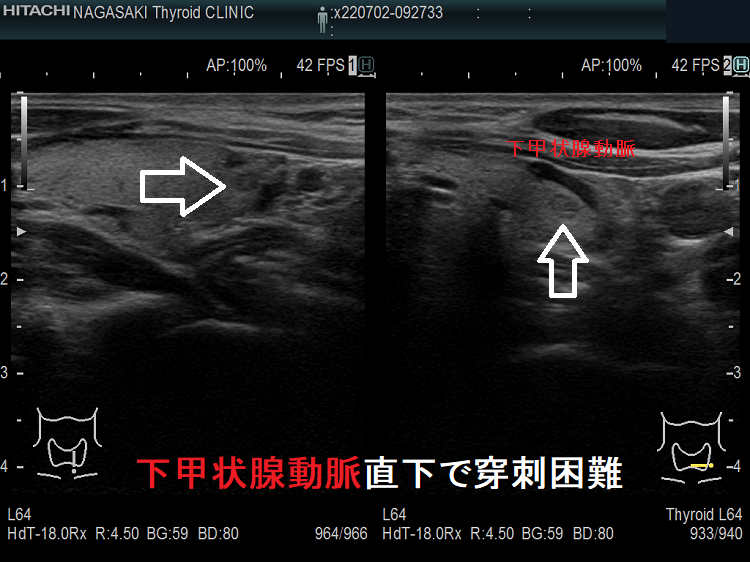

- 下甲状腺動脈直下で穿刺困難の小さな甲状腺腫瘍

甲状腺乳頭癌の可能性があるため、穿刺細胞診したくても、頚動脈や気管を刺してしまう危険を考えれば断念するのが正しいと思います。「退く勇気」も大切なのです。その代わり、甲状腺腫瘍が大きくならないか、腫瘍マーカーは上昇しないか、定期的に経過を見る必要があります。